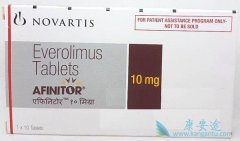

随着医疗技术的进步越来越多药物自诞生起就已经被赋予了多种疾病的治疗能力,其中依维莫司/飞尼妥就是一款治疗靶点众多的药物,除了晚期肾细胞瘤以外还可以治疗比如巨细胞瘤和结节性脑硬化等等疾病。但是面对不同的癌症疾病 飞尼妥副作用 也会有所不同, ...

据康安途海外就医了解到结节性硬化症(TSC)会引发相关的癫痫发作,目前这种疾病是一种比较罕见的遗传性疾病,很多患者都饱受癫痫发作的痛苦,因此我们治疗结节性硬化症(TSC)已经迫在眉睫,而作为癌症用药的依维莫司/飞尼妥在近段时间的海外医疗的研究中发 ...